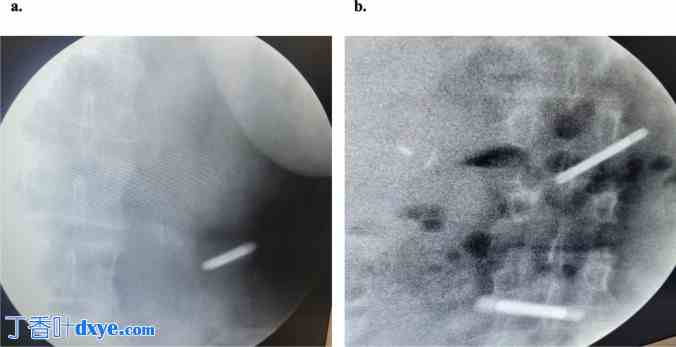

第一个(远端,回肠)磁体被吞咽。在X射线的监控下,其在胃和十二指肠中的运动受到监控。如果在X射线上,磁体在胃内不再可见,并且位于脊柱左侧(左胃系膜),则磁体已到达特赖茨韧带之外(图2a)。随后,可吞咽第二块近端(空肠)磁铁,两者之间间隔约2-3小时,具体取决于患者的胃肠蠕动。当两块磁铁均到达特赖茨韧带后(图2b),患者将被送至手术室并接受麻醉。

图 2.

磁体置入的 X 射线观察:a 如果胃内未检测到磁体,且在脊柱左侧(左胃系膜)可见,则磁体已超出特赖茨韧带;此后,可能吞咽第二块磁体;b 如果第二块磁体也超出特赖茨韧带;则患者被送往手术室进行麻醉和腹腔镜检查。